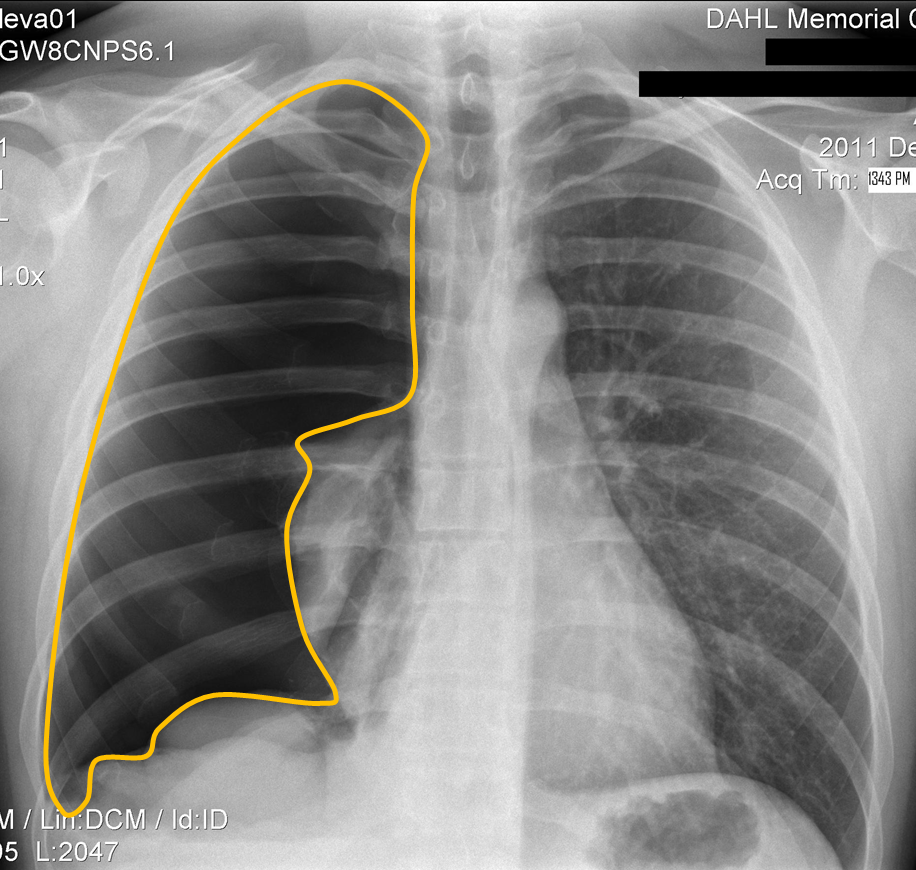

Which bronchus do inhaled foreign bodies tend to go down

Right Main Bronchus

slightly wider, shorter and more vertical